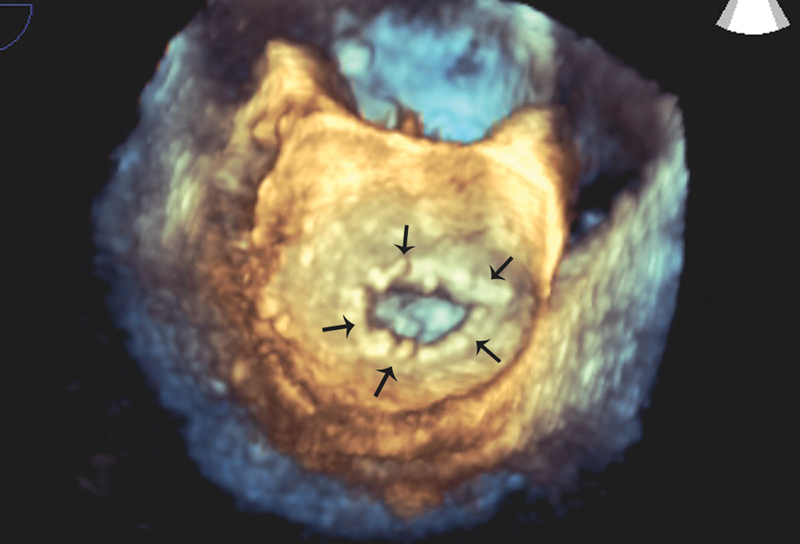

فحوصات تشخيصية لبعض امراض القلب والشرايين التاجية